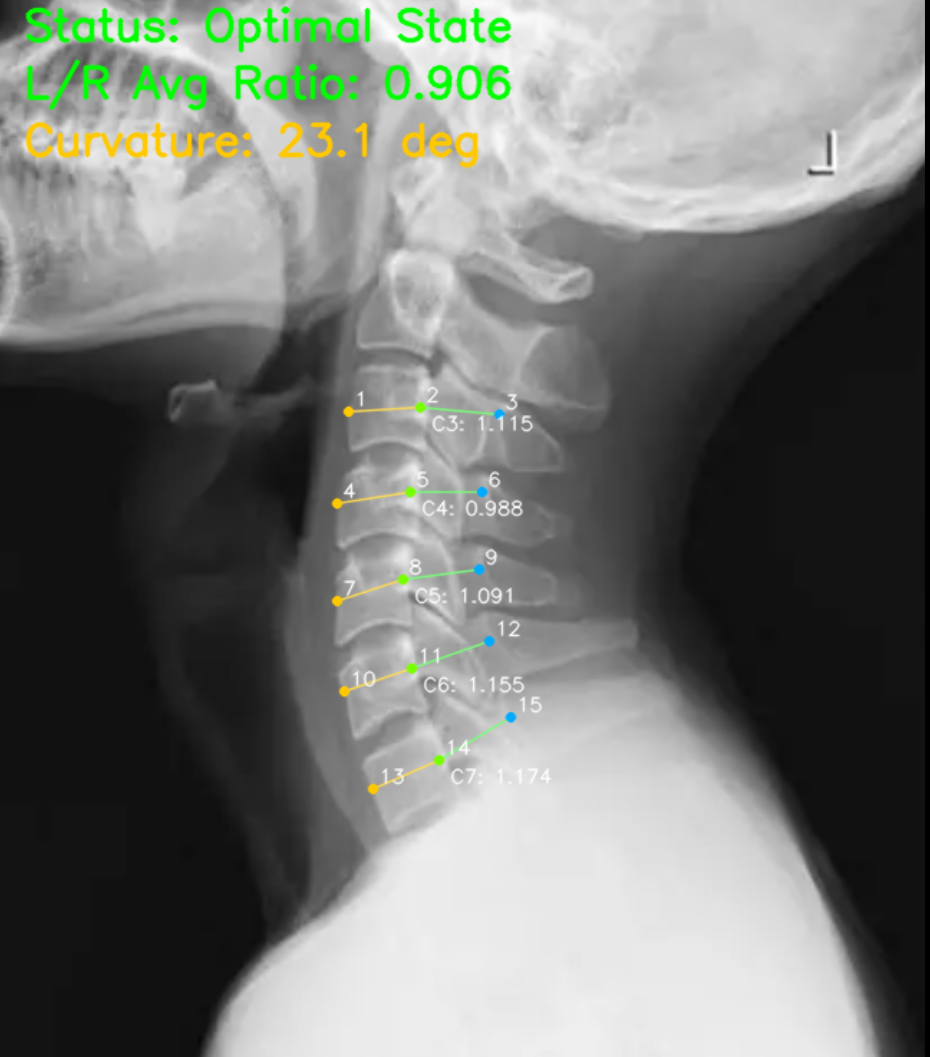

添加颈部X光识别,通过椎管与椎骨的量化标准评判颈椎的健康度。

颈椎椎管 精确标记例